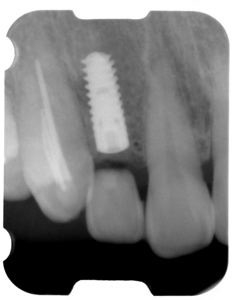

術後(レントゲン)、左下奥2本インプラント